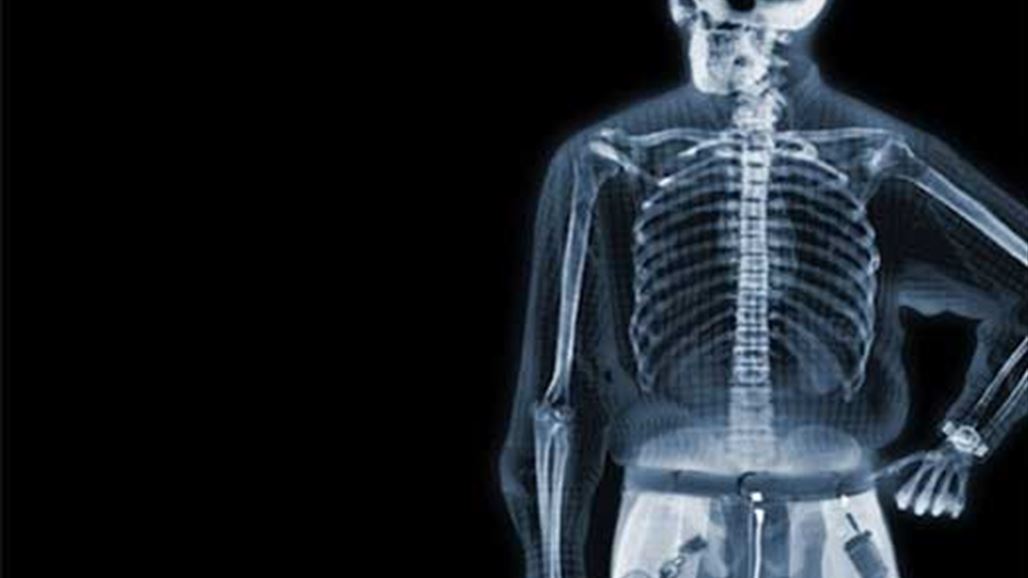

أجرى علماء في نيوزيلندا أول صورة ملونة بالأشعة السينية بالأبعاد الثلاثة على إنسان، مستعينين بتقنيّة من شأنها أن تحسّن التشخيص الطبي على ما قالت منظمة "سيرن" للفيزياء التي ساهمت في تكنولوجيا التصوير هذه.

وذكرت منظمة "سيرن" ان الصور تُظهر بوضوح تام الفرق بين العظام والعضل والغضروف، فضلاً عن حجم الأورام السرطانية وموقعها على سبيل المثال.